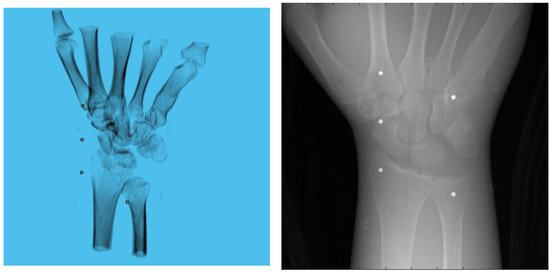

3. Experiments and Results

3.1. Simulation Setup